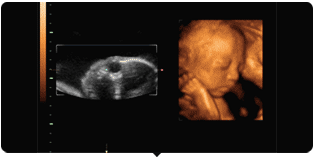

何为5D彩超?一堆专业术语帮主就不说了,简单些讲就是三星集团在二维、三维、四维超声的基础之上,研发出来的国际领先的彩超设备,5D彩超影像比四维彩超清晰度更高,诊断范围更全面,能够多方位、多角度地观察宫内胎儿的生长发育情况,为早期诊断胎儿先天性体表畸形和先天性心脏疾病提供准确的科学依据。

给你最直观的感受就是,成像效果超精细逼真!宝宝的彩超图像丰盈可爱,连他们细小的手指脚趾都能看清楚!

当然,这么高端的技术还是为了一件事:宝宝的健康!!!5D技术具有超高灵敏度的血流成像技术,能够检测到极其细小的末梢血管。新型的广角腔内探头,提供高达210度的扫查视野,方便腔内扫描。强大的数据处理和降噪能力,大大提高诊断的准确性。三维仿真成像速度更快,现实直观的诊断,也更方便医患及时沟通。

它的动态立体成像更直观更清晰,可对胎儿体表进行检查,同时对孕妇潜藏的各类疾病进行精确检测观察范围更广;能够多方位、多角度观察宫内胎儿生长发育情况,为早期诊断胎儿先天性体表畸形等疾病提供准确的科学依据。